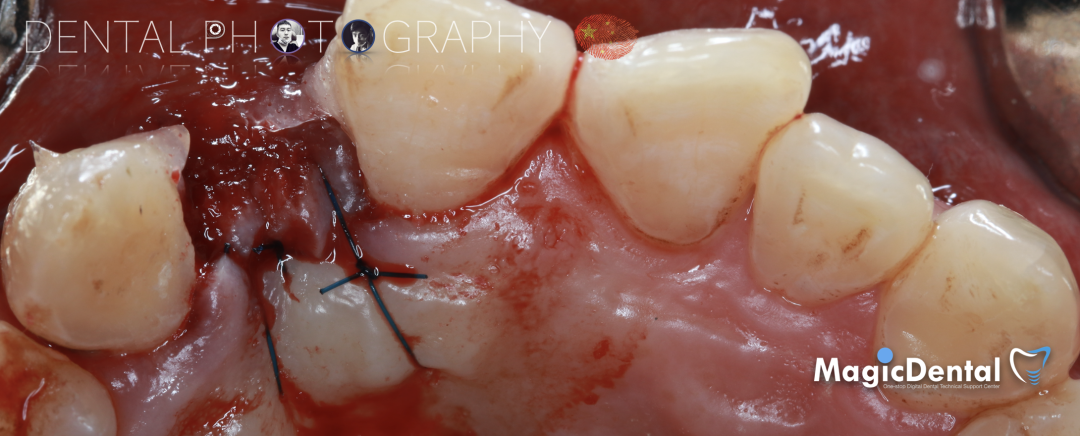

骨块细节

切开翻瓣,彻底暴露术区,试戴骨块。

调整骨块外形,适配受植区域,打开骨髓腔。

预备固位钉洞,固定骨块

骨膜减张,放置骨粉,放置骨块,钛钉固定骨块。

固定骨片,修整骨块边缘,继续放置骨粉覆盖骨块及受植区,放置骨膜,严密缝合创口。